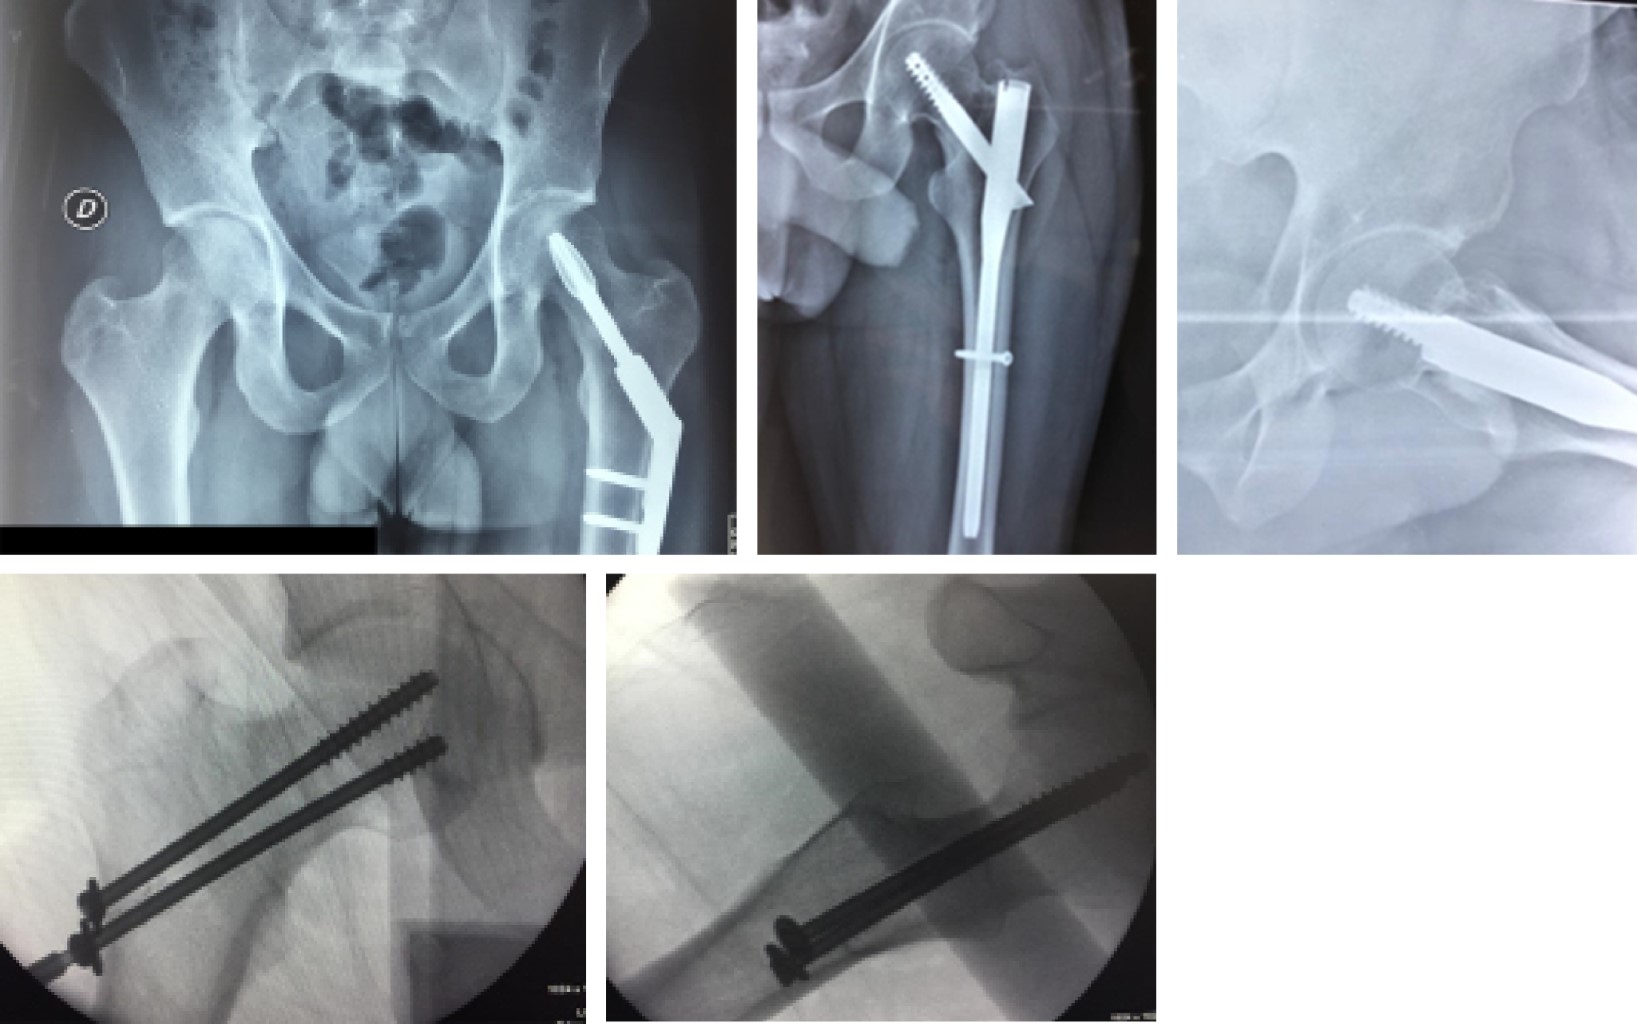

Stress hip fractures in men in military training

Introduction: Stress fractures are common injuries in the military population, they begin with the imposition of repetitive and excessive effort on the bone. This leads to the acceleration of bone remodeling and production of microfractures. The incidence, during their basic combat training, is 0.8 to 5.1% for men compared to 1.1 to 18% among women. We present a series of hip stress fractures in young male military men with progressive training of 8 hours a day over a period of 14 weeks. Results: Mean age 19.72 years, 4 transcervical and 7 basicervical fractures, 6 displaced and 5 no, 54.5 % right. All treated with osteosynthesis, DHHS (blockable compression plate system with hip spiral blade) in 3, cannulated screws in 3 and the proximal femoral fixation system with trochanteric nail (TFN) in five patients. The only common factor in all of them was intensive military training, pathology of metabolic or endocrine origin was ruled out. Onset of symptomatology measured in weeks with an average of 5. All patients had a delay in diagnosis with an average of 12.09 days at the time of definitive diagnosis. Conclusion: The diagnosis in stress fractures should be made based on clinical suspicion since the pain is insidious and in the report of the current condition patients fail to identify an exact moment as the onset of injury. The functional results were good and all of them managed to finish their military training.

Figure 2

Figure 3

Figure 4